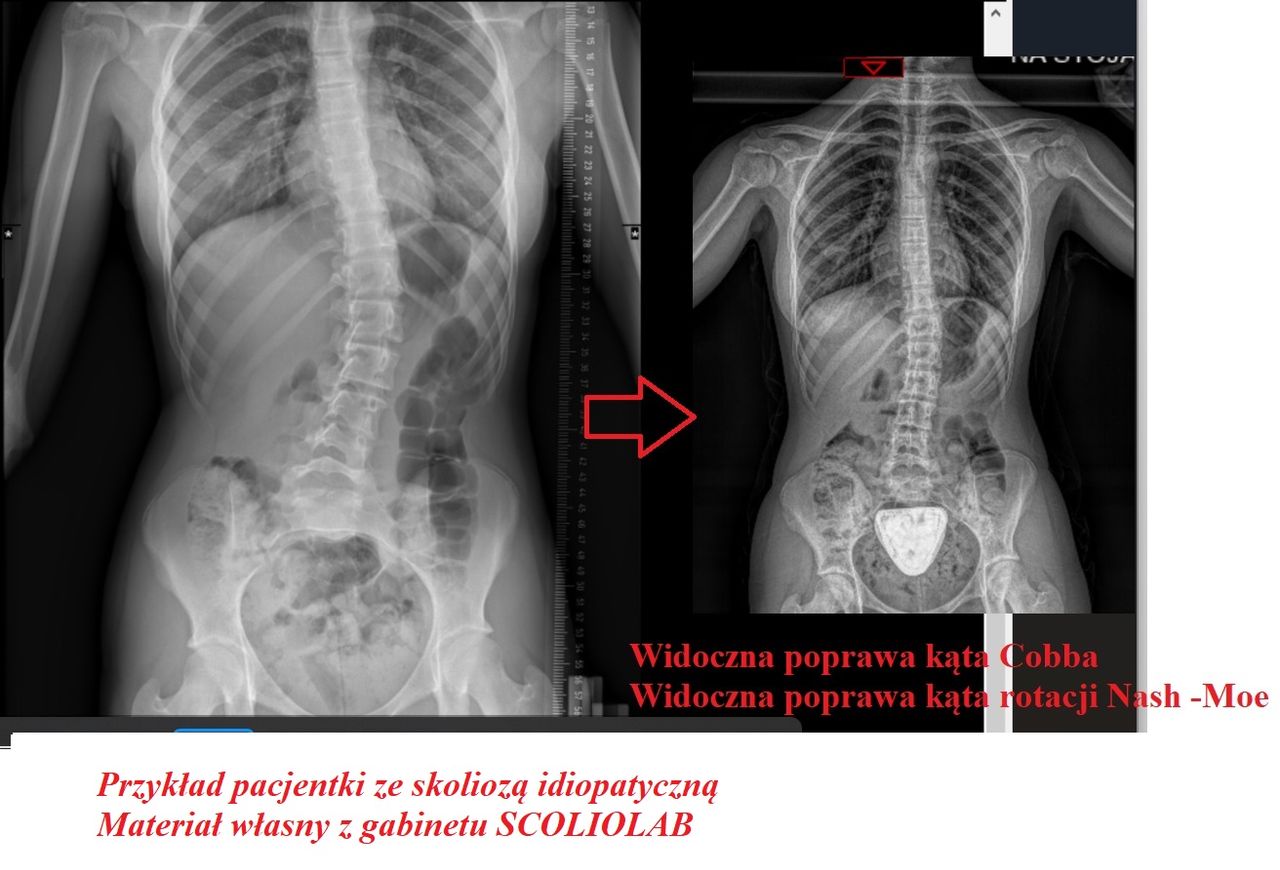

- Skolioza

Wizualna korekcja jest możliwa nawet i u starszych osób. Wszystko zależy od rodzaju i stopnia skoliozy. Odpowiednio dobrana terapia nie tylko poprawia komfort życia niwelując ból ale wpływa , na układ krążenia czy właśnie na wizualny aspekt postawy ciała.